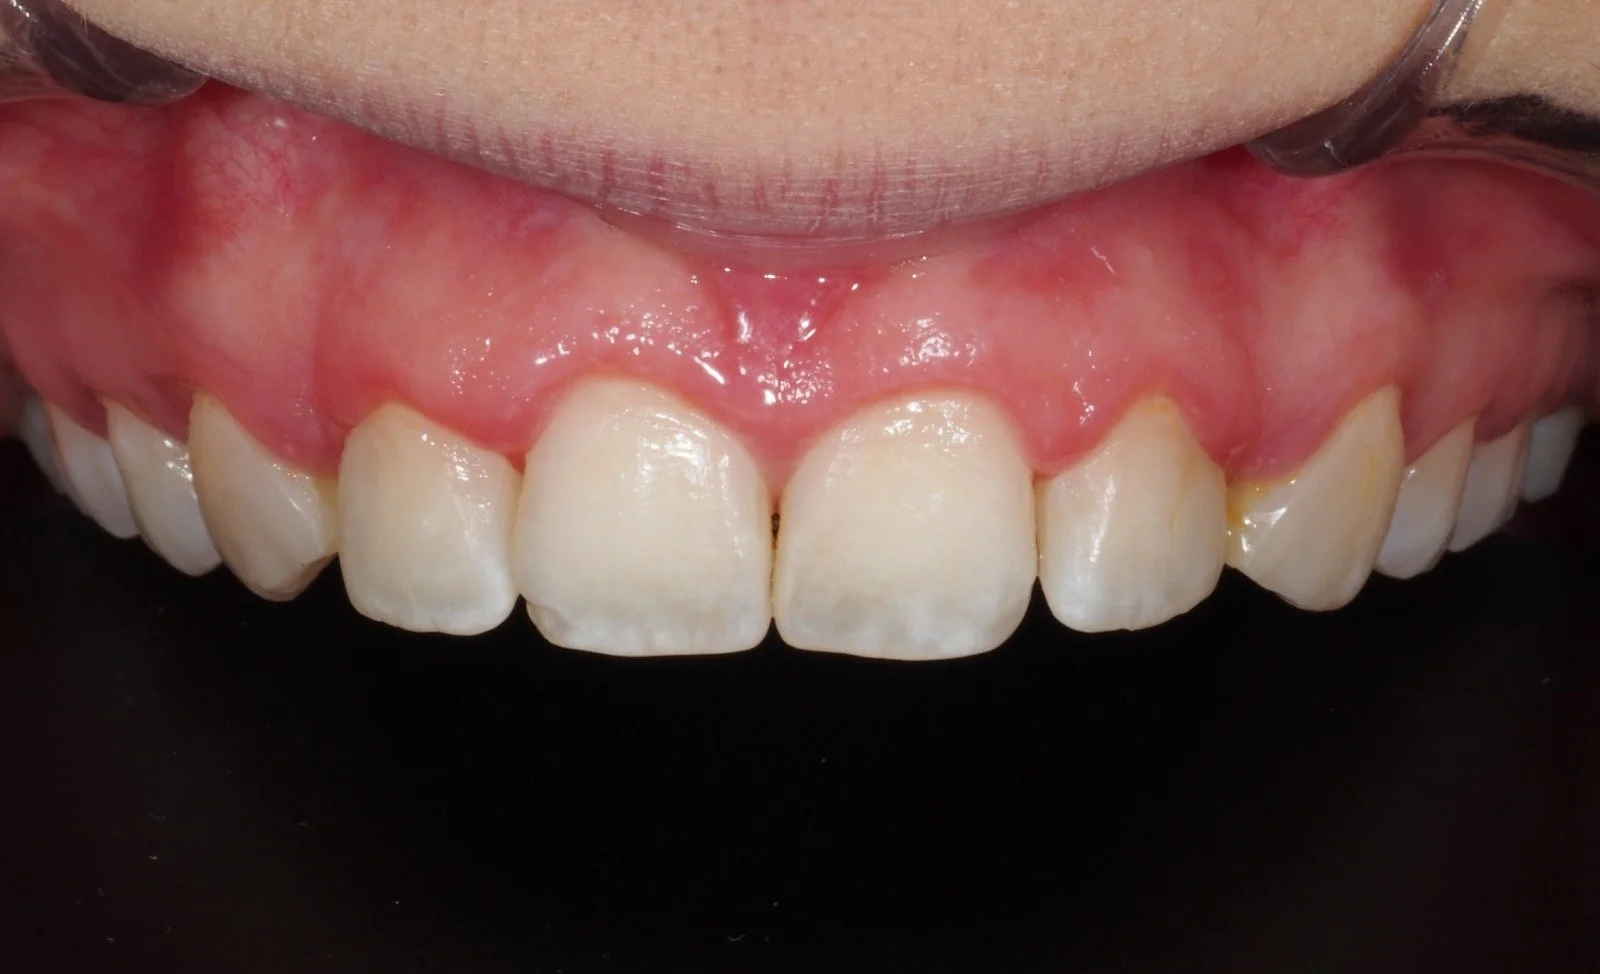

A nuestra clínica acuden pacientes con problemas de encías de sangrado, inflamación, sensibilidad, o retracción de encías que son tratados de forma individual, enseñándoles además como mantener las encías y mejorarlas, estableciendo un programa de citas de mantenimiento periódico.